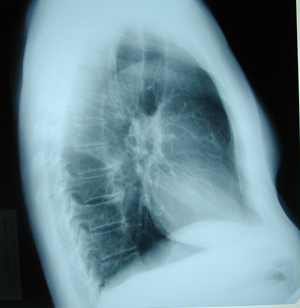

Figure 2

Lateral chest X-ray. A huge mass located in the right upper lobe, at the aortic arch level.